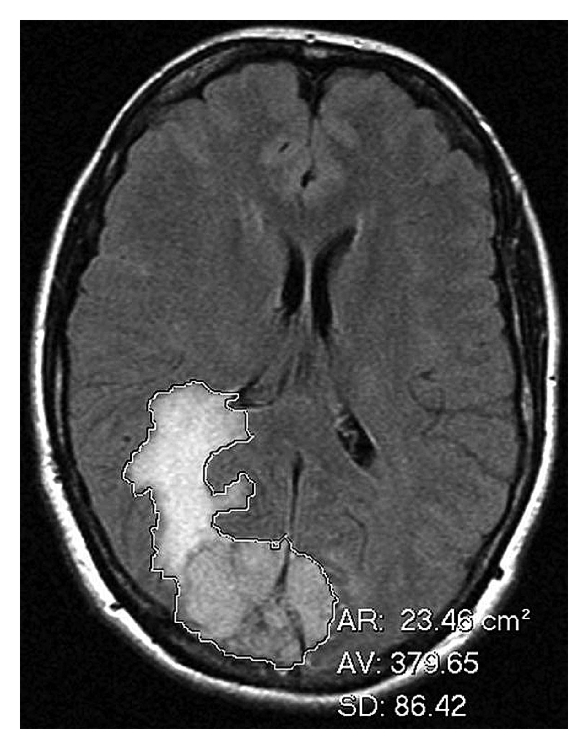

2.3.1. Peritumoral Brain Edema

The peritumoral brain edema index was defined as volume of tumor + volume of edema/volume of tumor. Volume measurements were obtained by using the freehand region of interest (ROI) tool on Kodak Carestream picture archiving and communication system (PACS) (Rochester, NY). After outlining the tumor and the tumor + edema on each slice of the FLAIR sequence a surface area was generated by the PACS (Figure 2). The surface area was multiplied by slice thickness to approximate the volume through that slice and all slice volumes were added to give total volume measurements.